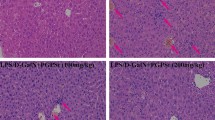

The results indicated that LPS/d-GalN administration markedly induced hepatic PKD activation, lethality and liver injury, while pretreatment of the PKD inhibitor Gö6976 significantly inhibited LPS-induced PKD activation, improved the survival of LPS/d-GalN-administered mice and attenuated LPS/d-GalN-induced liver injury, as evidenced by reduced levels of serum aminotransferases as well as reduced histopathological changes. In addition, the protective effects of Gö6976 were paralleled by suppressed activation of mitogen-activated protein kinases (MAPKs), decreased expression of tumor necrosis factor-α (TNF-α) and adhesion molecules, and reduced apoptosis and myeloperoxidase (MPO) activity in liver.